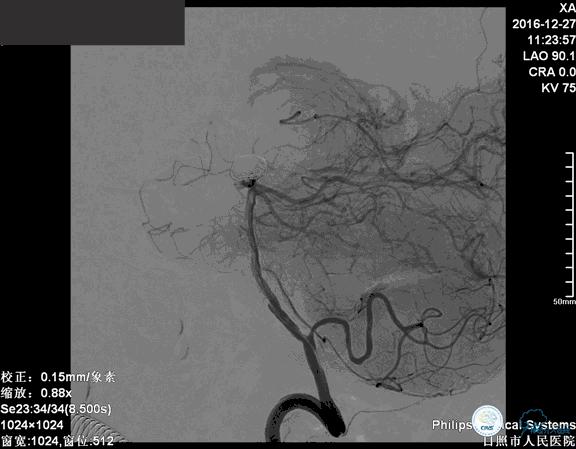

确诊:基底动脉顶端宽颈未破裂动脉瘤,动脉瘤大小约6mm×9mm,瘤颈约4毫米。

注:以下为动图

这是一例基底动脉顶端的宽颈未破裂动脉瘤,对未破裂动脉瘤治疗的主要依据就是除病人因素外,动脉瘤的大小、形态、部位是评估是否需要积极治疗的主要依据。

这个动脉瘤直径大于5毫米,位于基底动脉的顶端,形态不规则,具备破裂的高危因素。所以这个动脉瘤还是应该积极治疗。